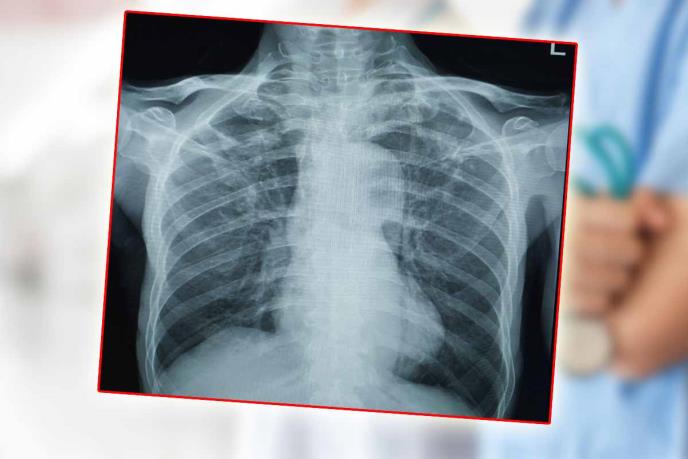

Čim je shvatio šta se desilo, zubar je svoje pacijentkinju odvezao u Urgentni centar, gde su joj lekari odmah snimili grudni koš i ustanovili gde se strano telo nalazi.